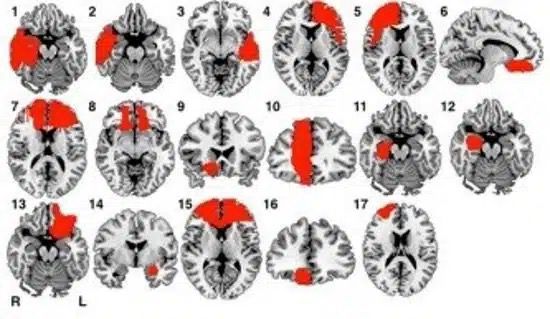

Le neuroscienze forensi hanno permesso di analizzare alterazioni cerebrali strutturali e funzionali nei soggetti con comportamenti criminali seriali. Le aree più frequentemente coinvolte sono:

1. Corteccia prefrontale: Coinvolta nei processi di controllo degli impulsi, empatia e giudizio morale. Nei serial killer, una ridotta attività nella corteccia prefrontale può tradursi in impulsività, scarsa capacità di pianificazione e assenza di rimorso.

2. Amigdala: Area chiave nella gestione delle emozioni, in particolare della paura e dell'aggressività. Uno sviluppo anomalo dell'amigdala è stato associato a ridotta risposta alla sofferenza altrui, tipica della psicopatia.

3. Sistema limbico: Responsabile dell'elaborazione emotiva e della memoria affettiva. In alcuni studi, i serial killer mostrano un iperfunzionamento limbico legato a una iper-sensibilità al rifiuto e alla frustrazione.

Per giunta, risonanze magnetiche funzionali (fMRI) hanno evidenziato schemi cerebrali atipici nella percezione del dolore e nell'attivazione dei centri della ricompensa durante la pianificazione di atti violenti.